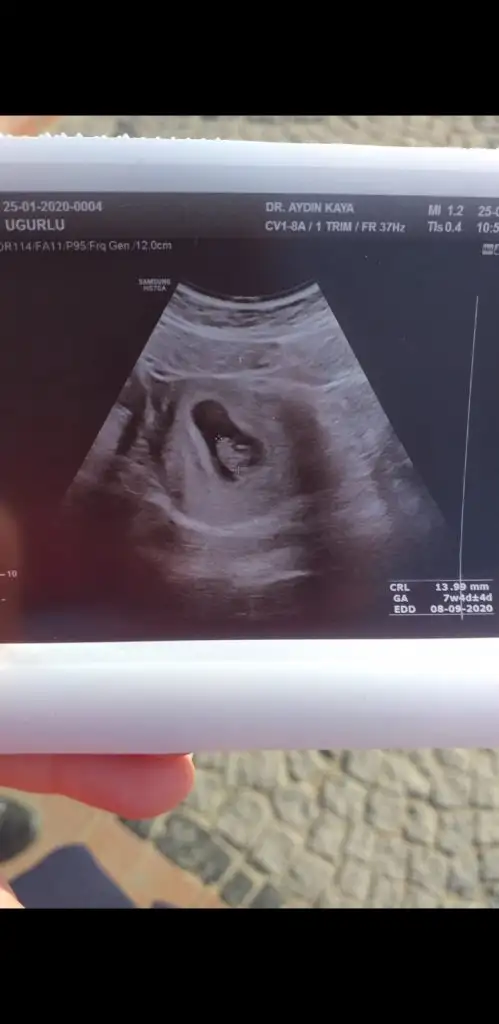

Her şey yolunda şimdilik, ilaçlara devam dedi boyu 14 mm olmuş 7+1 iz ama ultrasonda 7+4 çıktık, hareket ediyordu minigim, dr bu 20 gun çok riskli bir donem dedi, genelde bebeklere bisey oluyorsa bu 20 gün içinde oluyormuş, dikkat et dedi, ilişki son aya kadar serbest dedi, içim çok rahatladı, sizler nasılsınız? Her şey yolundadır umarim

• Screenshot_20200125-120502_WhatsApp.webp

13,9 KB · Görüntüleme: 86